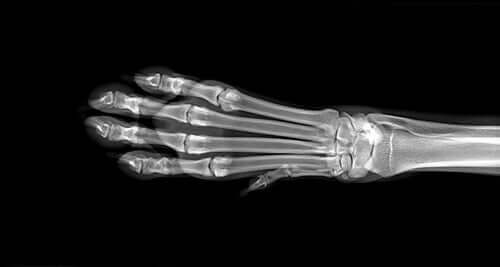

İlk olarak, veteriner şişliğin sebebini belirlemek amacıyla bir dizi test uygulayacaktır. Bunlar arasında kan ve idrar testleri ve muhtemelen eklemlerin röntgeninin çekilmesi yer alacaktır. Eğer bu testler kesin bir sonuç açıklamazsa, MR taraması gerçekleştirebilirler. Osteosarkom’dan şüphelenildiği durumlarda kemik biyopsisi gerçekleştirirler.